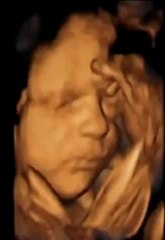

Dentro del útero, operan a un bebé que tenía una malformación